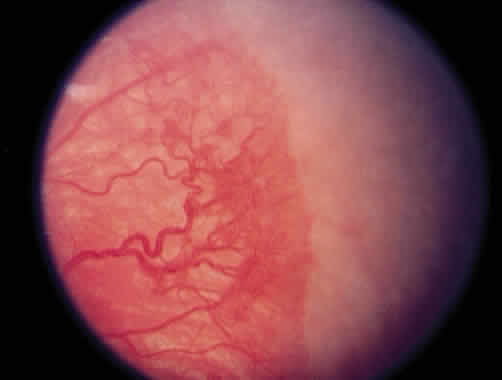

system effects. The most common form of regression of ROP is continued growth of the retinal vasculature anteriorly with gradual fading of the disease at the border of posterior vascularized and anterior avascular retina. Another more dramatic sign of regression is the growth of vessels beyond the ridge (Fig. 1). The vessels penetrate into the avascular retina as an arteriole with an accompanying venule. As the vessels grow beyond the ridge, the dilation and tortuosity of vessels just posterior to the shunt and in the posterior pole diminish.